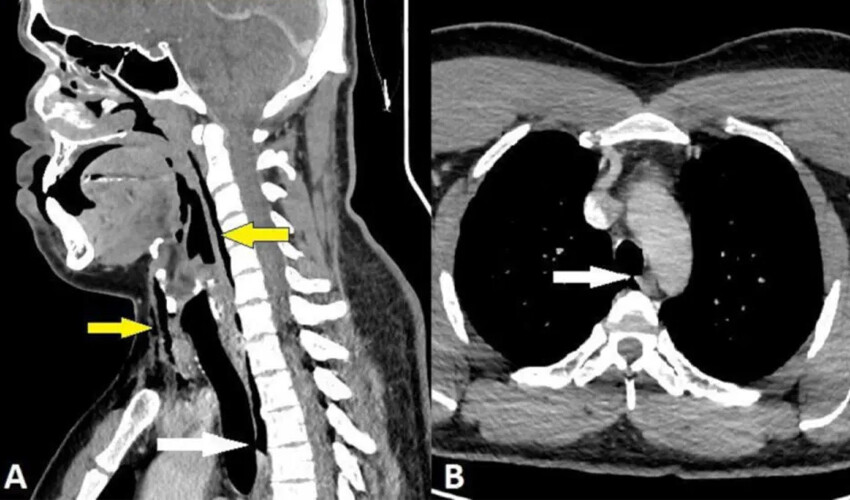

Röntgen filmi ise yırtığın boynun üçüncü ve dördüncü kemikleri arasında olduğunu ve adamın göğsündeki akciğerler arasındaki boşlukta hava biriktiğini gösterdi.